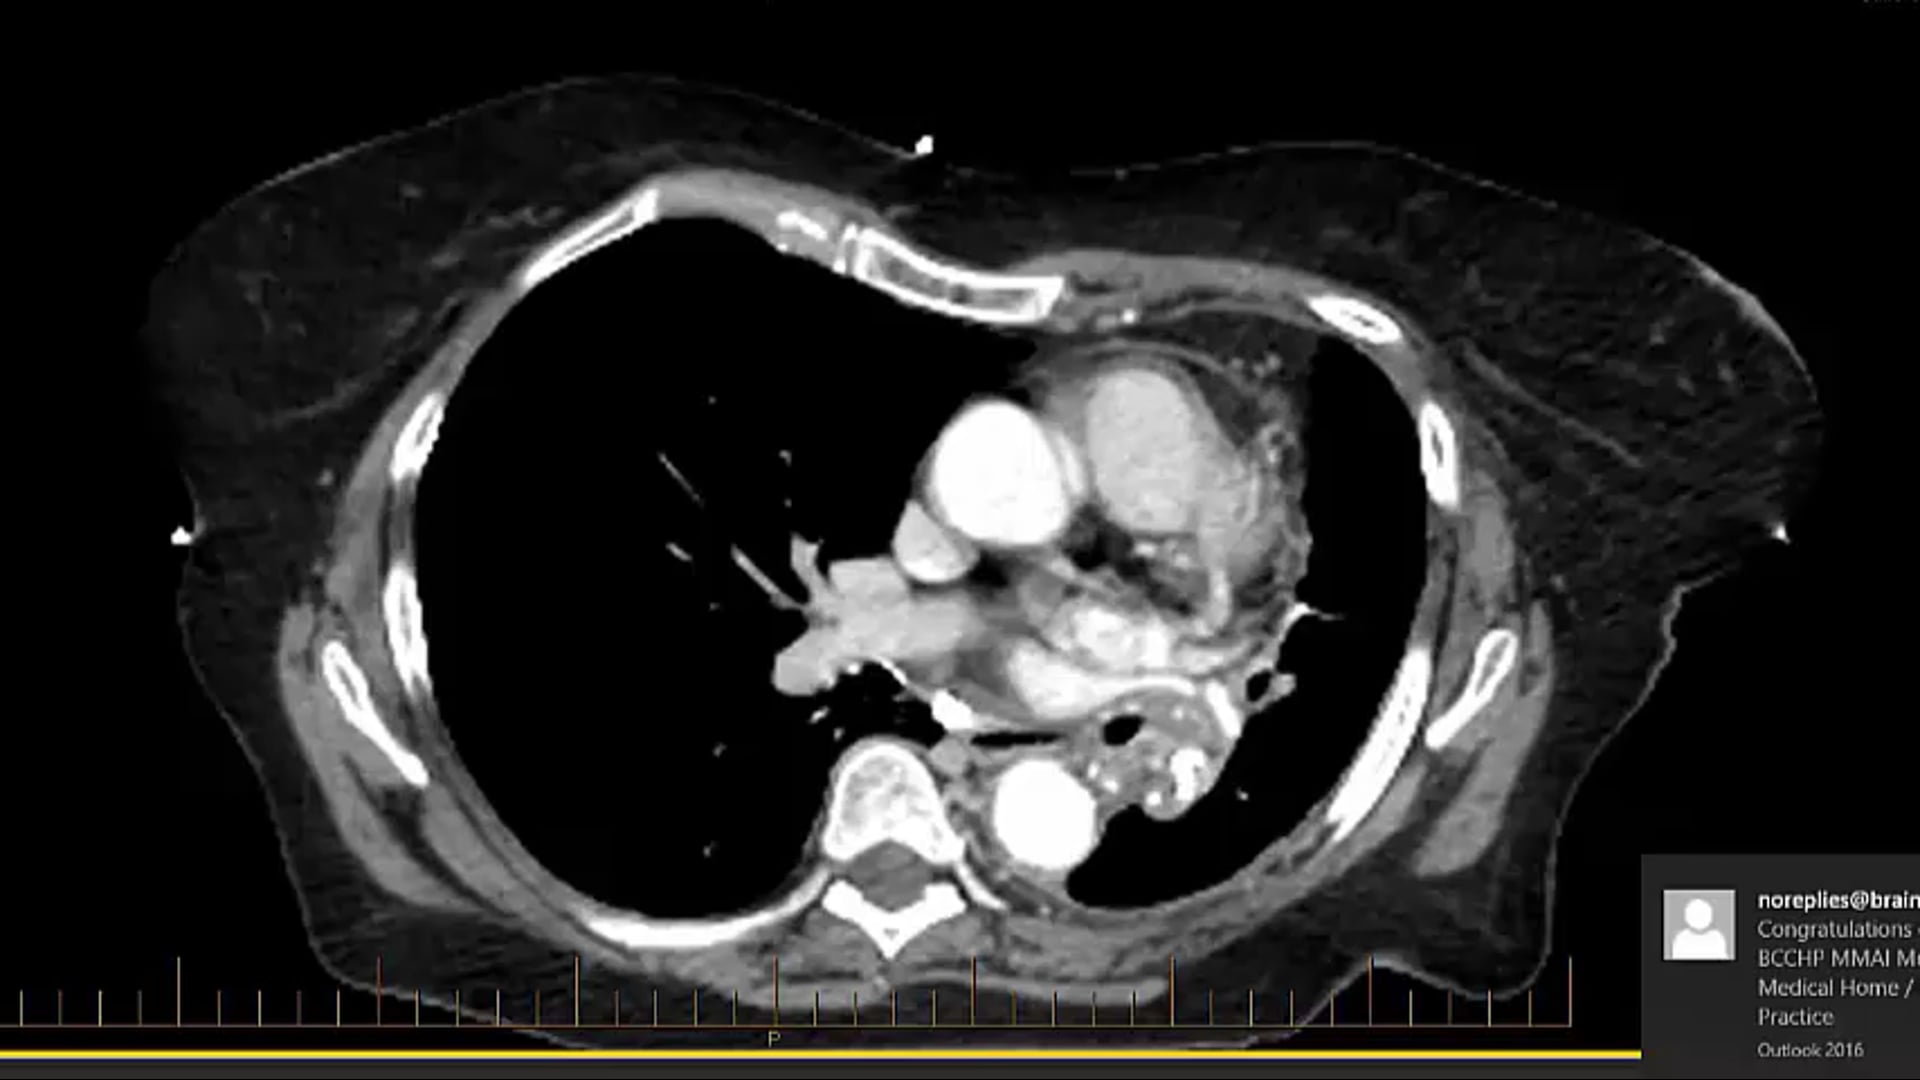

10/06/2022 - Dr. Candice Johnstone - Radiation Oncology - Lung/Esophageal

refused chemotherapy, tumor, dose-volume constraints, CORSAIR, 55Gy 20 regimen, SBRT, CTV, clinical target volume, fractionation